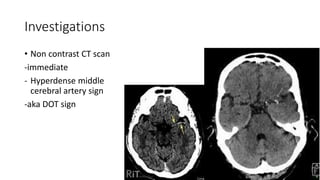

• Non contrast CT scan

-immediate

- Hyperdense middle

cerebral artery sign

-aka DOT sign